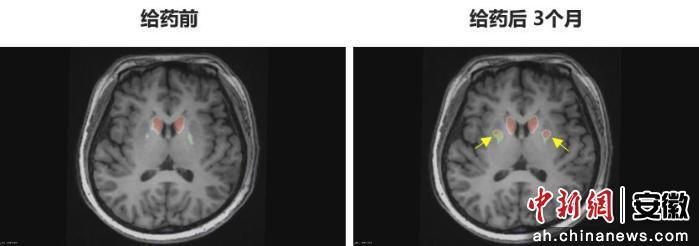

“身體不僵硬了,像正常人一樣?!崩钆啃χf。多年的抖動與“關(guān)期”徹底消失,她重新感受到身體的輕盈和心靈的自由。術(shù)后影像顯示,移植細胞已在腦內(nèi)成功定植并發(fā)揮功能,醫(yī)生稱這些“亮點”是新生多巴胺能神經(jīng)元的直接證據(jù)。

圖為李女士 PET-DAT/MRI融合圖像術(shù)前與術(shù)后三個月對比。

圖為李女士?PET-DAT/MRI融合圖像術(shù)前與術(shù)后三個月對比。